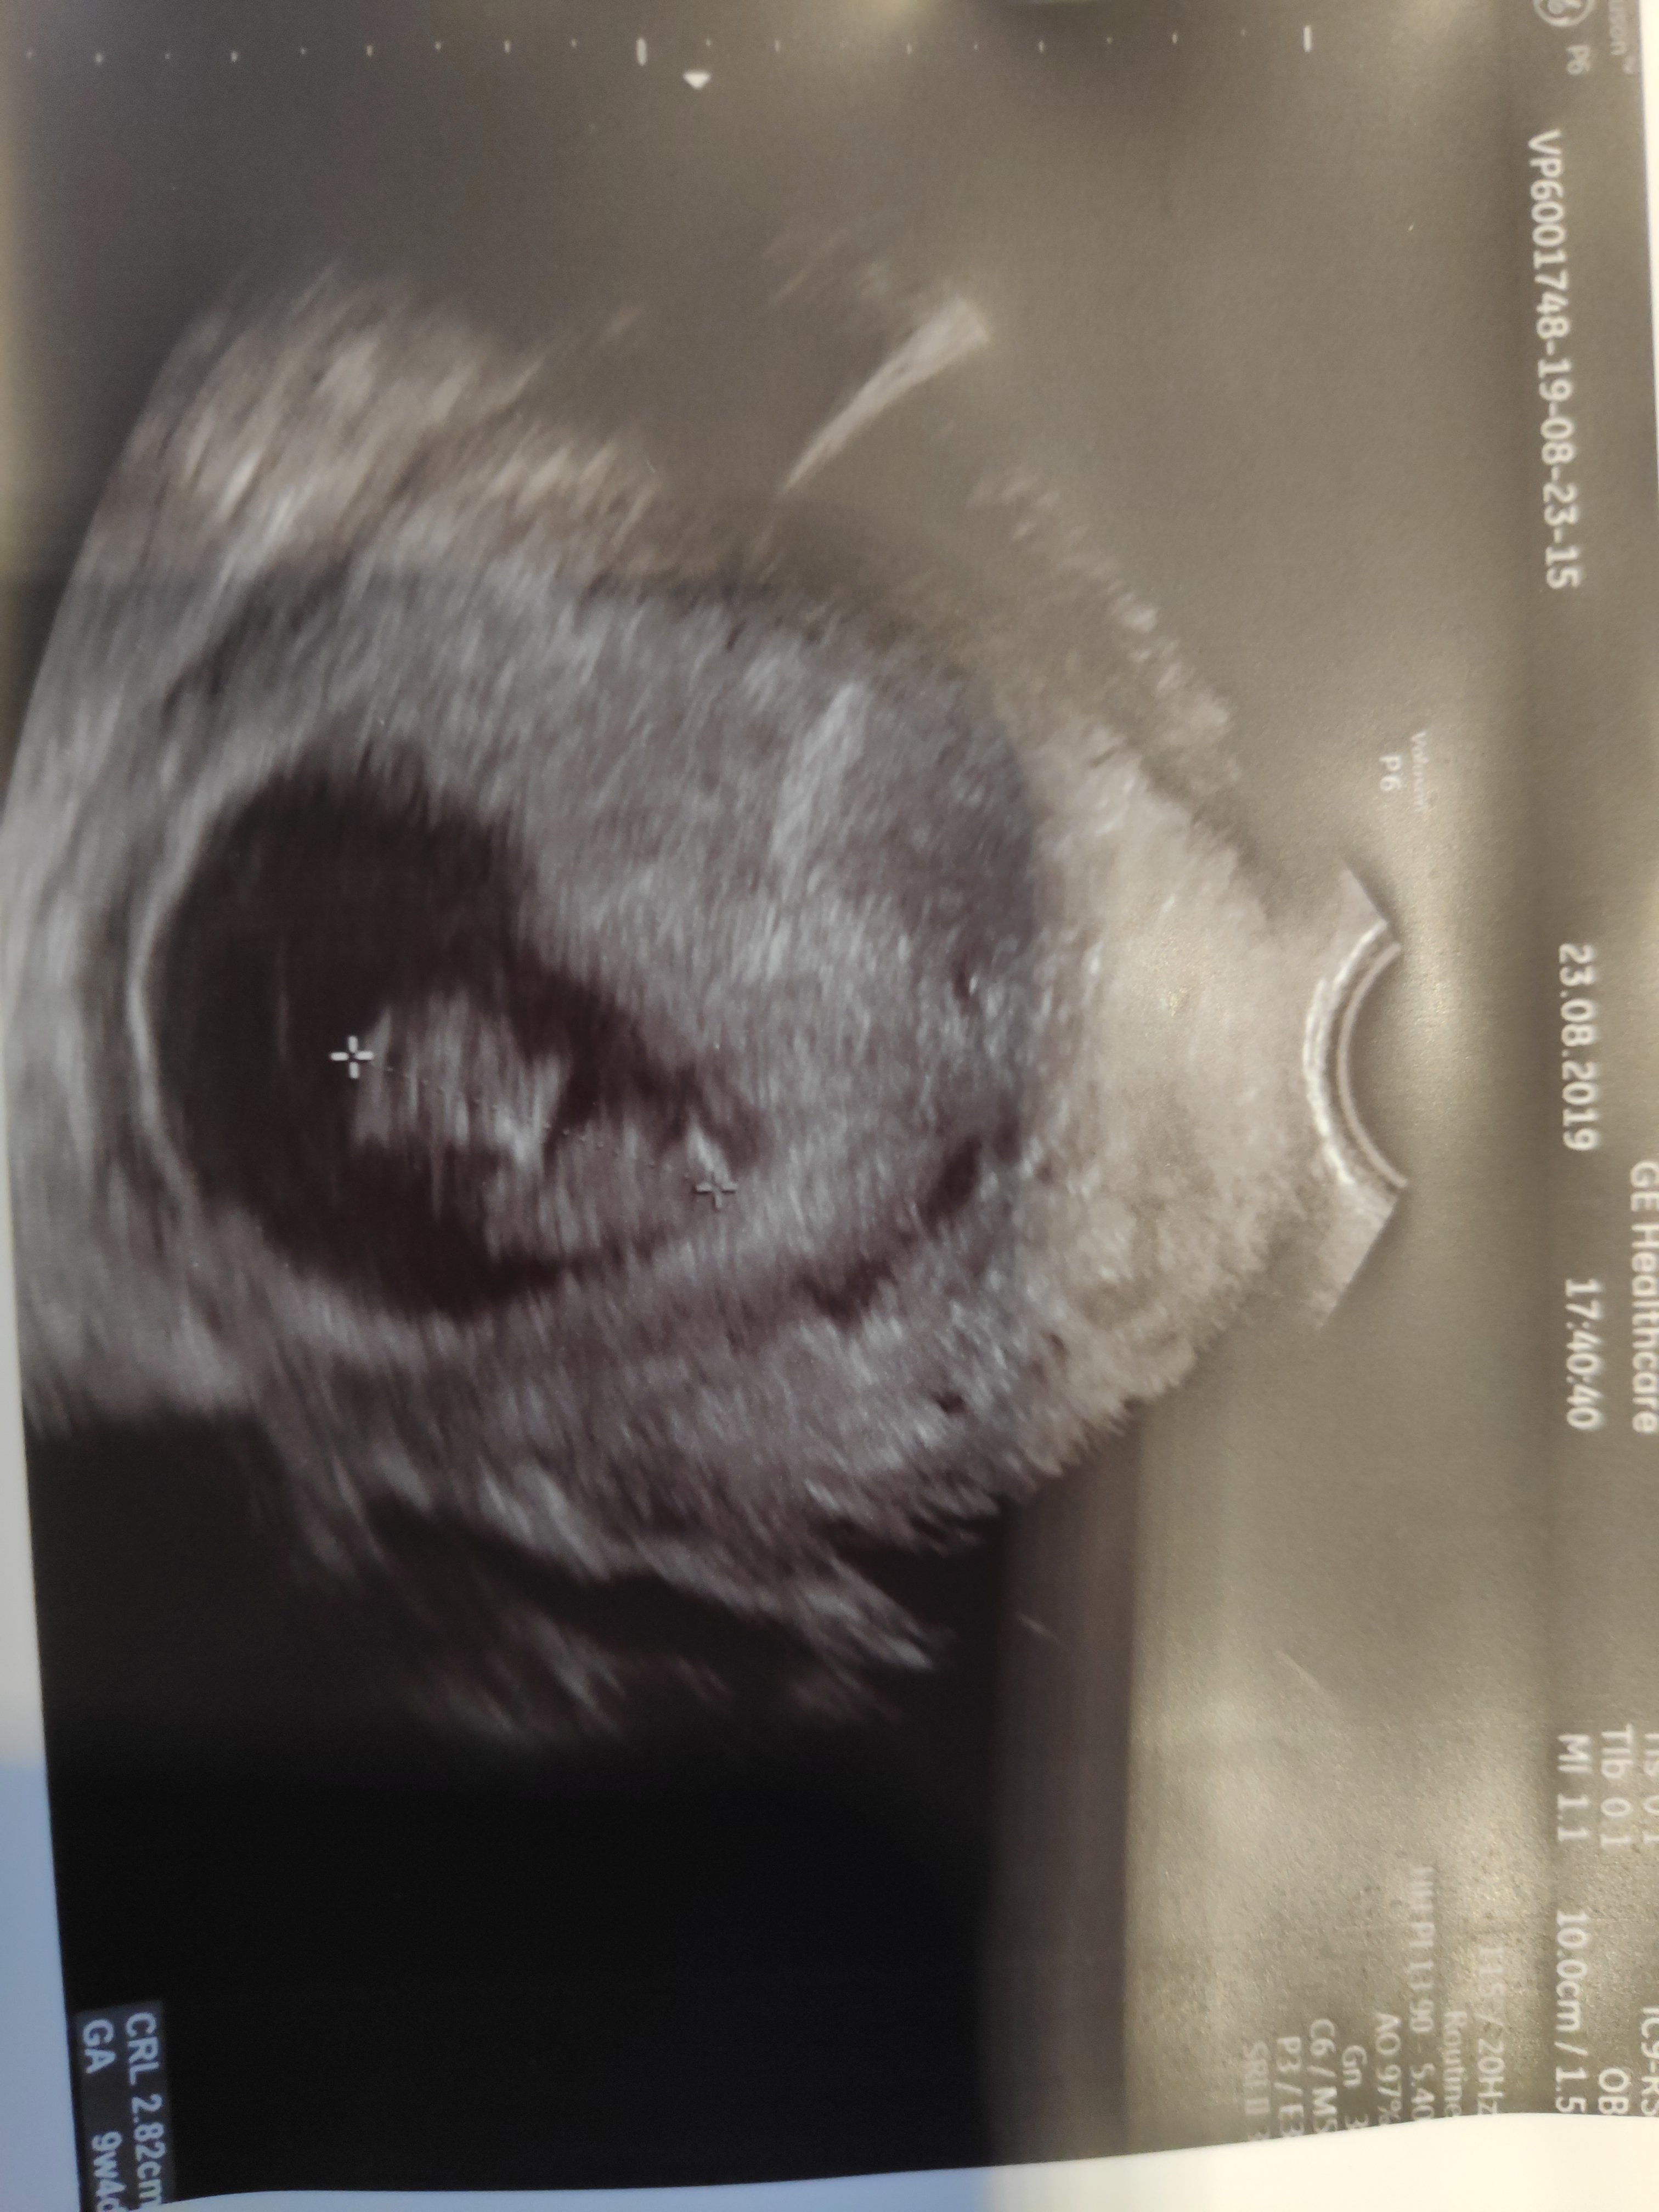

Wy widzicie tak jak ja głowę oczko nosek rączki i nóżki moja rodzina i mój mąż i moja córka do mnie ze to żółwik oni nic nie widzą mówią jakąś plama mama to spanikowala że to takie zniekształcone....